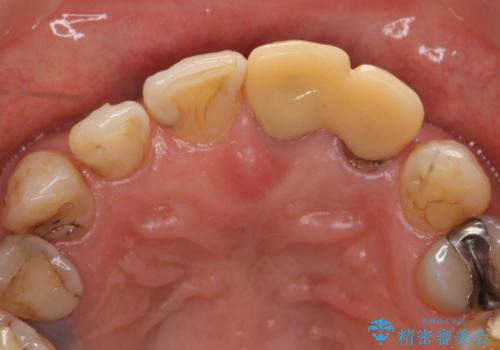

- 左側の前歯の見た目が気になるといらっしゃった方の症例です。

左上1、2番目の歯は仮歯の状態だったので外して状態を確認したところ、左上2は垂直的な歯根破折を認めたため抜歯となりました。左上1は再根管治療を行いました。

左上2抜歯後、骨および歯肉の回復を待ち、オールセラミッククラウンのブリッジによる欠損補綴を行いました。